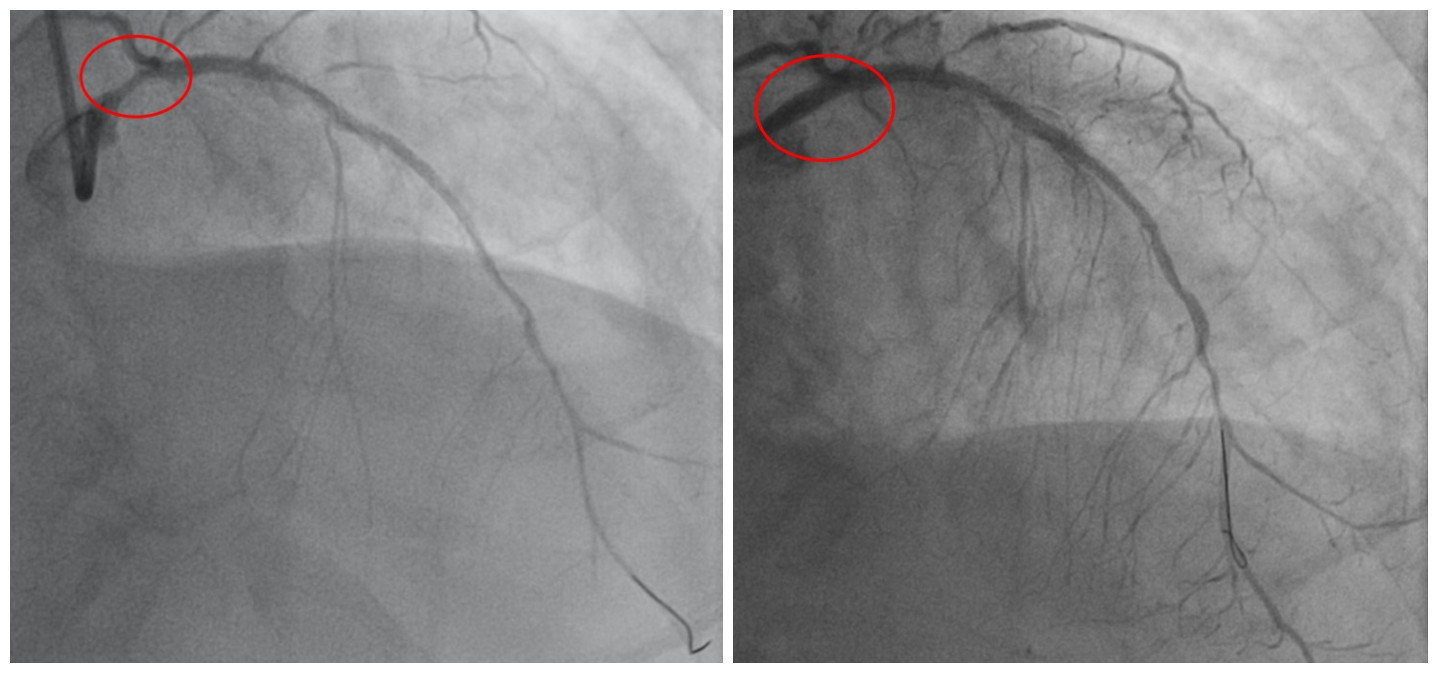

术前、术后检查结果显示,韩先生冠脉支架内在狭窄的问题被解决

韩先生到医院检查发现,心脏主要三根大血管狭窄病变严重,原来植入药物支架内也再次狭窄,

导致心脏严重缺血。近一个月来,韩先生辗转多家医院,均被建议做冠脉搭桥术,但考虑到冠脉搭桥手术恢复、住院周期长、风险大,他十分犹豫,但病情逐渐加重,韩先生不得不考虑接受手术,遂到湖南省人民医院心血管内科,准备控制心衰后做冠脉搭桥术。

认为左主干狭窄90%,原支架内再狭窄是导致患者心衰根本原因,因而解决支架内再狭窄是当务之急,可以在原支架内狭窄部位再次植入药物支架,避免搭桥手术,与患者和家属充分沟通后,制定了微创介入治疗方案。

潘宏伟主任分析患者心脏仅靠“一丝”血流维持血供,且球囊扩张狭窄处时心脏无法再次耐受缺血,随时可发生心脏骤停等危险,在团队紧密配合下,最终在数分钟内迅速在左主干狭窄部位植入药物支架、原支架内行球囊扩张术,成功解除了再狭窄问题,恢复心脏血流挽救生命。